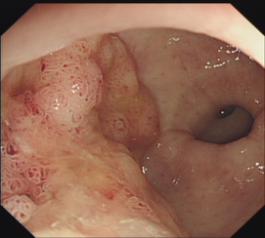

結(jié)腸腺瘤粘膜剝離術(shù)